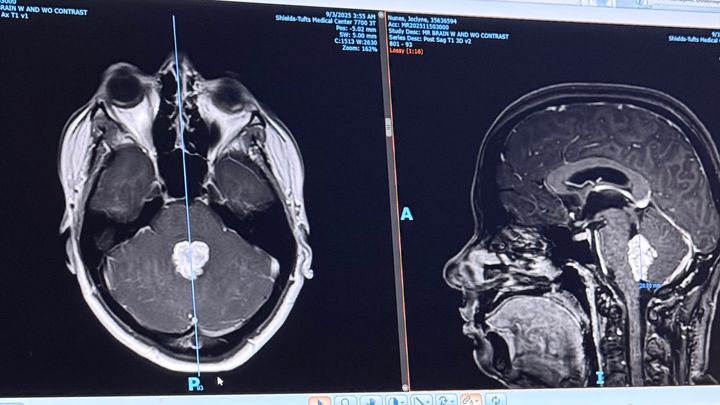

I am SO incredibly thankful that they did this, as it was determined that I had a nose-sized brain tumor - a choroid plexus papilloma with CSF obstruction. Me, someone who is young, healthy, and relatively active. I had some concerns, but I definitely didn’t expect to have a brain tumor that would need immediate removal.

36 hours later, I underwent brain surgery. I am thrilled to say that the entire tumor has been removed and is believed to be benign. Further genetic testing is being completed and I have a follow-up appointment in the coming days.